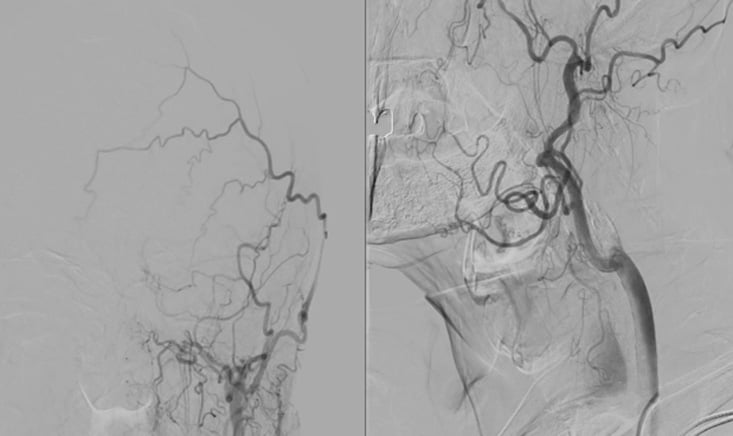

Supra-aortic trunks angiography

Occlusion of the left internal carotid artery

Subocclusive stenosis of the right internal carotid artery